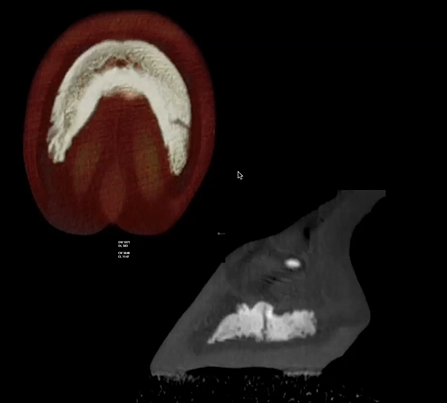

Read MoreThis is a navicular case with more severity in the right front limb. CT images show deep synovial invagination, sclerosis, and distal boarder fragmentation. Featured: Dr. Diego De Gasperi, University of Wisconsin-Madison